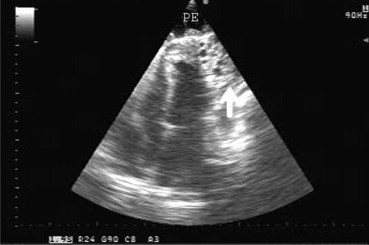

Electrocardiogram showed negative T waves in the inferior and lateral leads. A laboratory analysis revealed leukocytosis (12,700/mm3 with 63% eosinophils), erythrocyte sedimentation rate of 90 mm/hour, and elevated levels of creatine kinase MB (63.5 ng/mL), fibrinogen (12.4 g/L), C-reactive protein (168.5 mg/L), creatinine (420 μmol/L), creatine kinase (2806 IU/L), aspartate aminotransferase (69 IU/L), and alanine aminotransferase (61 IU/L). Transthoracic echocardiography demonstrated a large pericardial effusion (3.3 cm behind the left ventricle posterior wall, 4 cm ahead of the apex, and 3.1 cm ahead of the right ventricle) with signs of right ventricle compression and cardiac tamponade, multilayered appearance of the periventricular pericardium, and 55 mm × 66 mm round multilocular cystic mass adjacent to the apical and apicolateral segment of the left ventricle (Fig. 1).

Transthoracic four-chamber echocardiographic view showing the large pericardial ...

Figure 1.

Transthoracic four-chamber echocardiographic view showing the large pericardial fluid and multilocular cyst (marked with arrow).